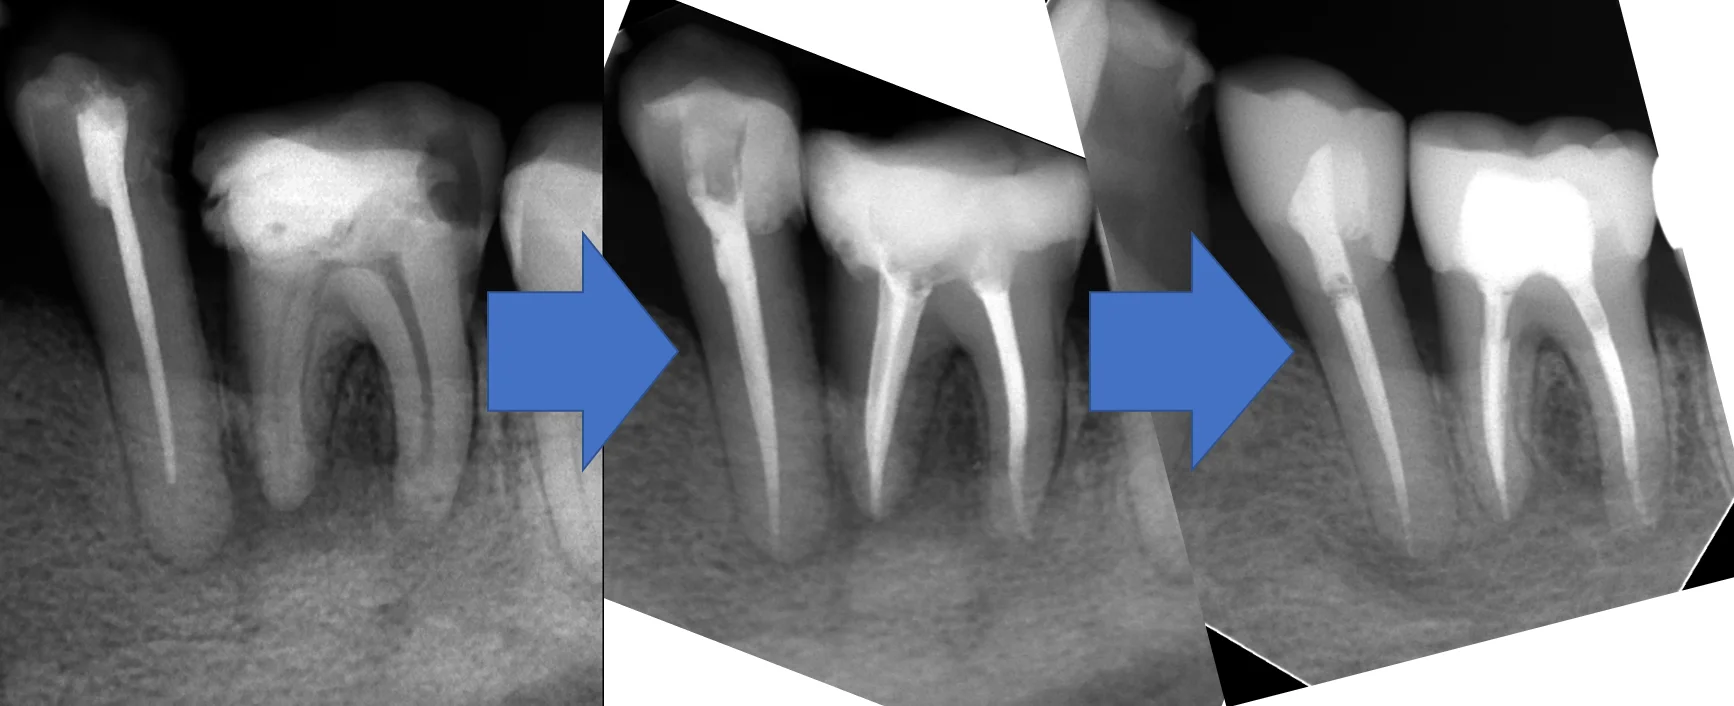

術前・術後・術後1年で並べるとこんな感じです。

その後も痛みなどもなく問題なく過ごすことが出来ているそうで、ホッとしております。